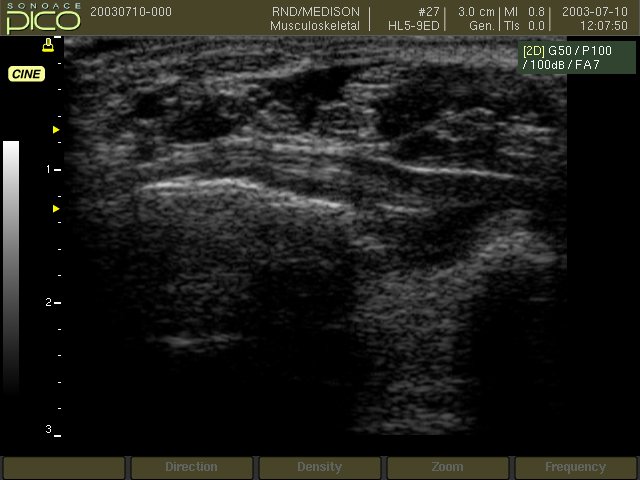

Области применения: акушерство и гинекология, абдоминальные исследования и маммология, урология и эхокардиография, поверхностно расположенные органы и исследования сосудов, мускуло-скелетные исследования, а также педиатрия.

Линейный датчик 5-12 МГц

Поверхностные структуры (щитовидная железа, молочная железа, лимфоузлы), мускулоскелетные исследования (суставы, мышцы, подкожные структуры), периферические сосуды.

Линейный датчик 5-9 МГц